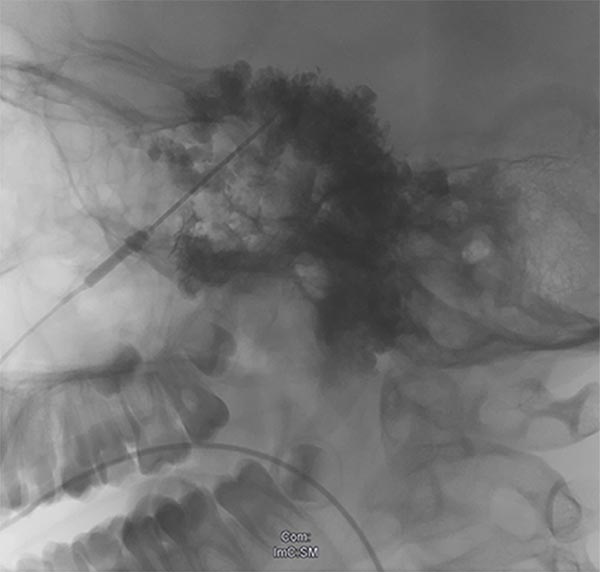

X-ray after direct injection of contrast medium into the venous malformation via 2 puncture needles. No outflow via any communication veins, good needle position for sclerotherapy. Now 2 ml of Aethoxysklerol 3% 1:4 admixed with air (foam sclerotherapy) are injected.

X-ray after injection of contrast medium into the venous malformation during the 2nd sclerotherapy 8 months later. Again no outflow via communicating veins is displayed. Good needle position for another foam sclerotherapy (3 ml Aethoxysklerol 3%, foamed 1:4 with air).

X-ray after injection of contrast medium into the venous malformation, for what is now the third sclerotherapy treatment after pain recurrence. Almost the entire remaining venous malformation is contrasted by contrast injection at the current needle position. Now 4.5 ml of Aethoxysklerol 3%, foamed 1 to 4 with air, is injected.